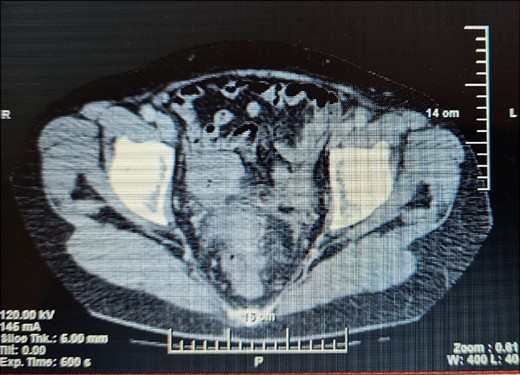

A 63-year- old women was admitted to the surgical department with right abdominal pain radiating to the right inguinal region and low back, and the pain had worsened in the last month. Because of these complains a magnetic resonance imaging was performed on an outpatient basis and a thickening of the sigmoid along a length of ~4 cm was found. The patient tells about a benign education, for which the necessary documentation is missing. Colonoscopy was performed which revealed edema and hyperemia of the mucosa ~20 cm from anorectal line to pseudopolypoid dilated lymphatic vessels as in a malignant process. Three biopsies were performed, the result of which proved the presence of moderately inflamed changes and marked lymphostasis with dilated lymphatics. Given the colonoscopy finding and the inability to rule out a malignant process despite a negative biopsy, a contrast- enhanced computed tomography of the abdomen and pelvis was performed. Examination showed a circumferentially and irregularly thickened intestinal bowel wall up to 15 mm ~ 11 cm from the anorectal line along ~6 cm concentrically stenosing lumen, increasing its density characteristic unevently and mainly on the periphery, compacted perirectal fatty tissue, diverticulosis along the sigmoid course, enlarged, regional lymph nodes up to 14/12 mm (Fig. 1). The blood count showed no abnormalities. Given the suspicions of the presence of a malignant process in the sigmoid, the patient underwent surgery and a thickening was found in the sigmoid area and pericolic adipose tissue with infiltration to the right ovary and right ureter. En block resection of the sigmoid along with the right ovary was performed, which was densely attached to the right ureter. On cutting a macroscopic specimen, the cartilaginous density of the tumor along a length of ~6 cm/d and stenosing the lumen of the intestine was impressed, which confirmed our suspicions of malignancy (Fig. 2). Contrary to our expectations, the histological result proved a complicated colonic diverticulitis with exacerbation, abscessation and spread of the inflammatory process with involvement of the pericolic tissues and right ovary, lymph nodes with mixed reactive lymphadenitis. The patient was followed twice with fibrocolonoscopy and with nuclear magnetic resonance postoperatively, which did not show any pathological changes.